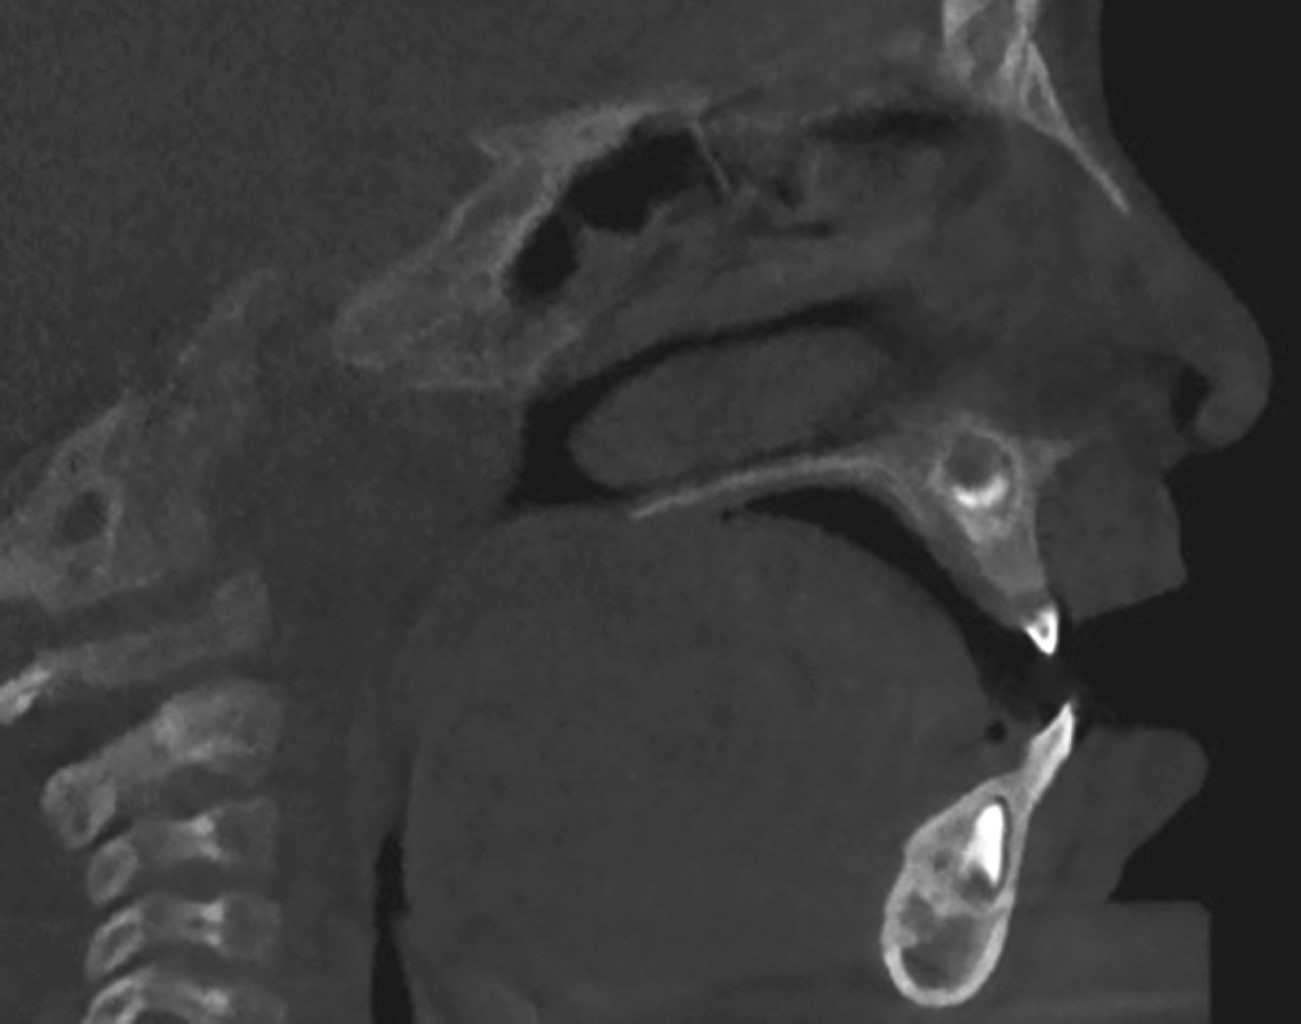

La macroglosia es una afección caracterizada por el aumento del tamaño de la lengua causado por malformaciones congénitas como linfangiomas, corioestomas, hamartomas, o malformaciones adquiridas como neoplasias benignas o malignas. En la mayoría de los casos, el tratamiento es quirúrgico y puede ser conservador cuando la vía aérea no está comprometida. En este trabajo presentamos el caso de un paciente varón de dos años con diagnóstico de macroglosia por linfangioma. El protocolo de tratamiento consistió en una glosectomía parcial mediante la técnica de resección en cuña estelar y colgajo de rotación anterior, así como terapia del habla tras la fase quirúrgica. Tras un año de seguimiento, se observó la persistencia de la lesión, lo que mereció una segunda intervención quirúrgica en la que se consiguió una dimensión lingual de parámetros normales, preservando la armonía estética y funcional sin causar alteraciones neurosensoriales ni gustativas.

Figura 1